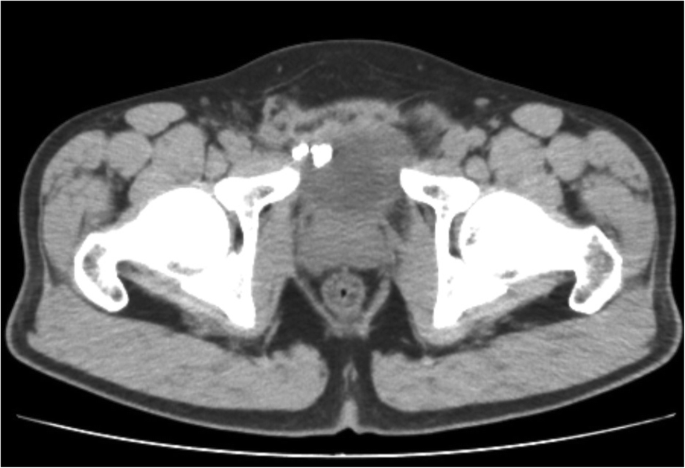

A 37-year-old man was referred to our clinic in December 2019 with the chief complaint of recurrent frequency, urgency and odynuria for 3 months. Routine urinalysis showed 102 WBC/ul and 21 RBC/ul), but the result of urine culture was negative. Ultrasound of the urinary system revealed bladder stones attached to the anterior bladder wall and further abdominal CT-scan showed the existence of bladder stones and calcified tissues around the right inguinal region (Fig. 1). Subsequent cystoscopy demonstrated bladder stones and part of the eroded mesh on the right anterior wall (Fig. 2). The patient received open mesh repair for right inguinal hernia in September 2014, which recurred 9 months after the previous surgery, for which a TAPP repair was performed in May 2015. According to the second operation, a hernial orifice about 3 cm was identified on the right inguinal region, for which a 6 cm × 13 cm polypropylene mesh (COOK, USA) was applied and fixed with four non-absorbable metallic tacks on the dorsal side of the Cooper’s ligament and the pubic bone. In February 2019, the patient came to our clinic primarily with dysuria and hematuria for 2 days. CT scan identified urethral and bladder stones, for which a day-case transurethral cystoscopic holmium laser lithotripsy was performed. During the fragmentation, we found that the mesh was partially eroded and therefore cut the eroded portion by holmium laser under cystoscopy.